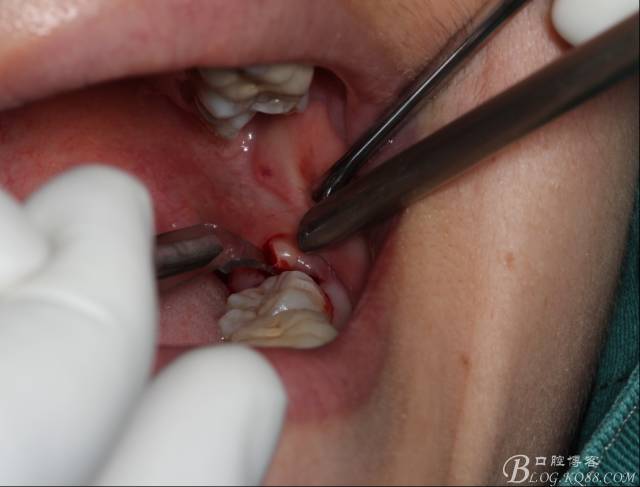

補完牙后,準備撥除阻生智齒了。

先分析智齒的情況,口內(nèi)直觀是半個牙尖都沒露出來,差一點就完全埋伏了。磨牙后墊的可操作面積中規(guī)中紀,X全景片示三類阻生,根冠比例是1:1,非融合根,近中根壓下頜管。

切開:角形切口,這個位置切開我喜歡更易操作12#刀。